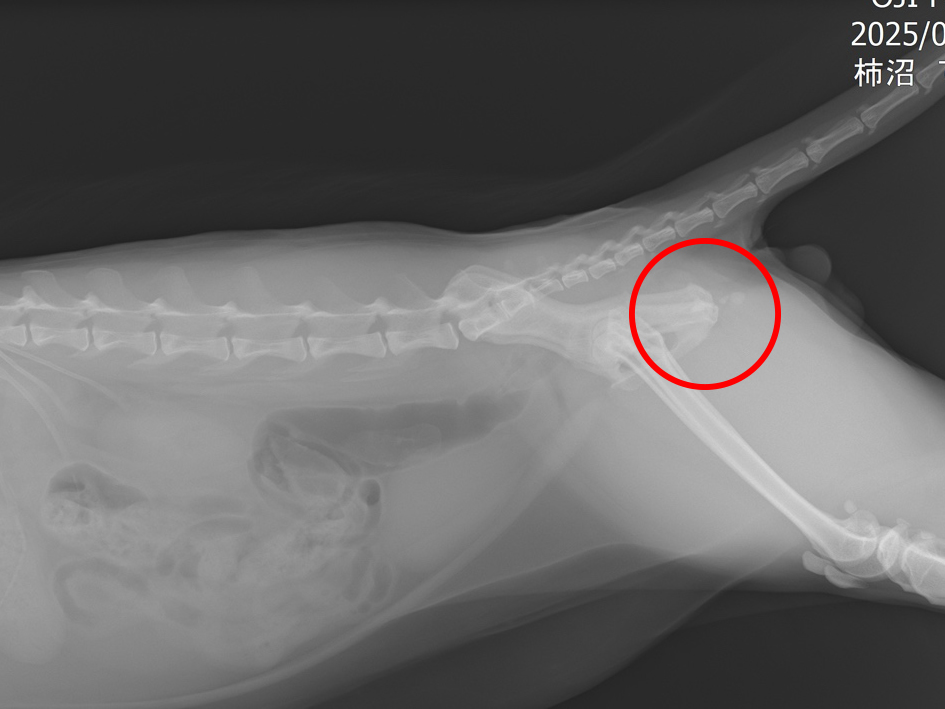

レントゲン検査を行ったところ、尿道の中にたくさんの結石が見つかりました。そこで、麻酔をかけて結石を膀胱の中に戻し、内視鏡を使った腹腔鏡手術で膀胱の結石を取り除く治療を行いました。

レントゲン画像にて尿道の結石の個数を確認